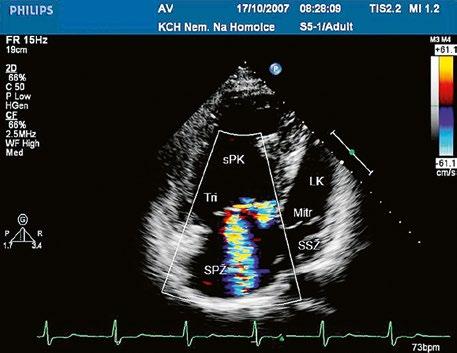

Poslechový nález systolického šelestu nad plicnicí s fixním rozštěpem 2. ozvy je nenápadný. Echokardiograficky je patrná dilatovaná a objemově přetížená pravá komora s paradoxním pohybem septa (Obr. 45.9), zkratový tok může být vidět i transtorakálně (TTE) (Obr. 45.10, Video 45.3, Video 45.7), ale suverénní diagnostickou metodou je jícnová echokardiografie (TEE), případně s 3DE zobrazením (Obr. 45.1, Obr. 45.2,

Obr. 45.10 TTE, čtyřdutinová apikální projekce s levo pravým zkratem na úrovni síní (šipka) při defektu septa síní typu secundum PK – pravá komora, LK – levá komora, LS – levá síň, PS – pravá síň